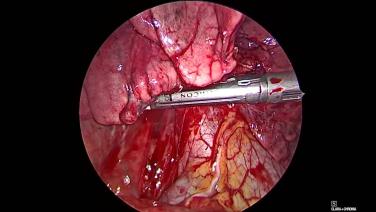

Thorascopic Lobectomy - Staple and Divide the Pulmonary Artery